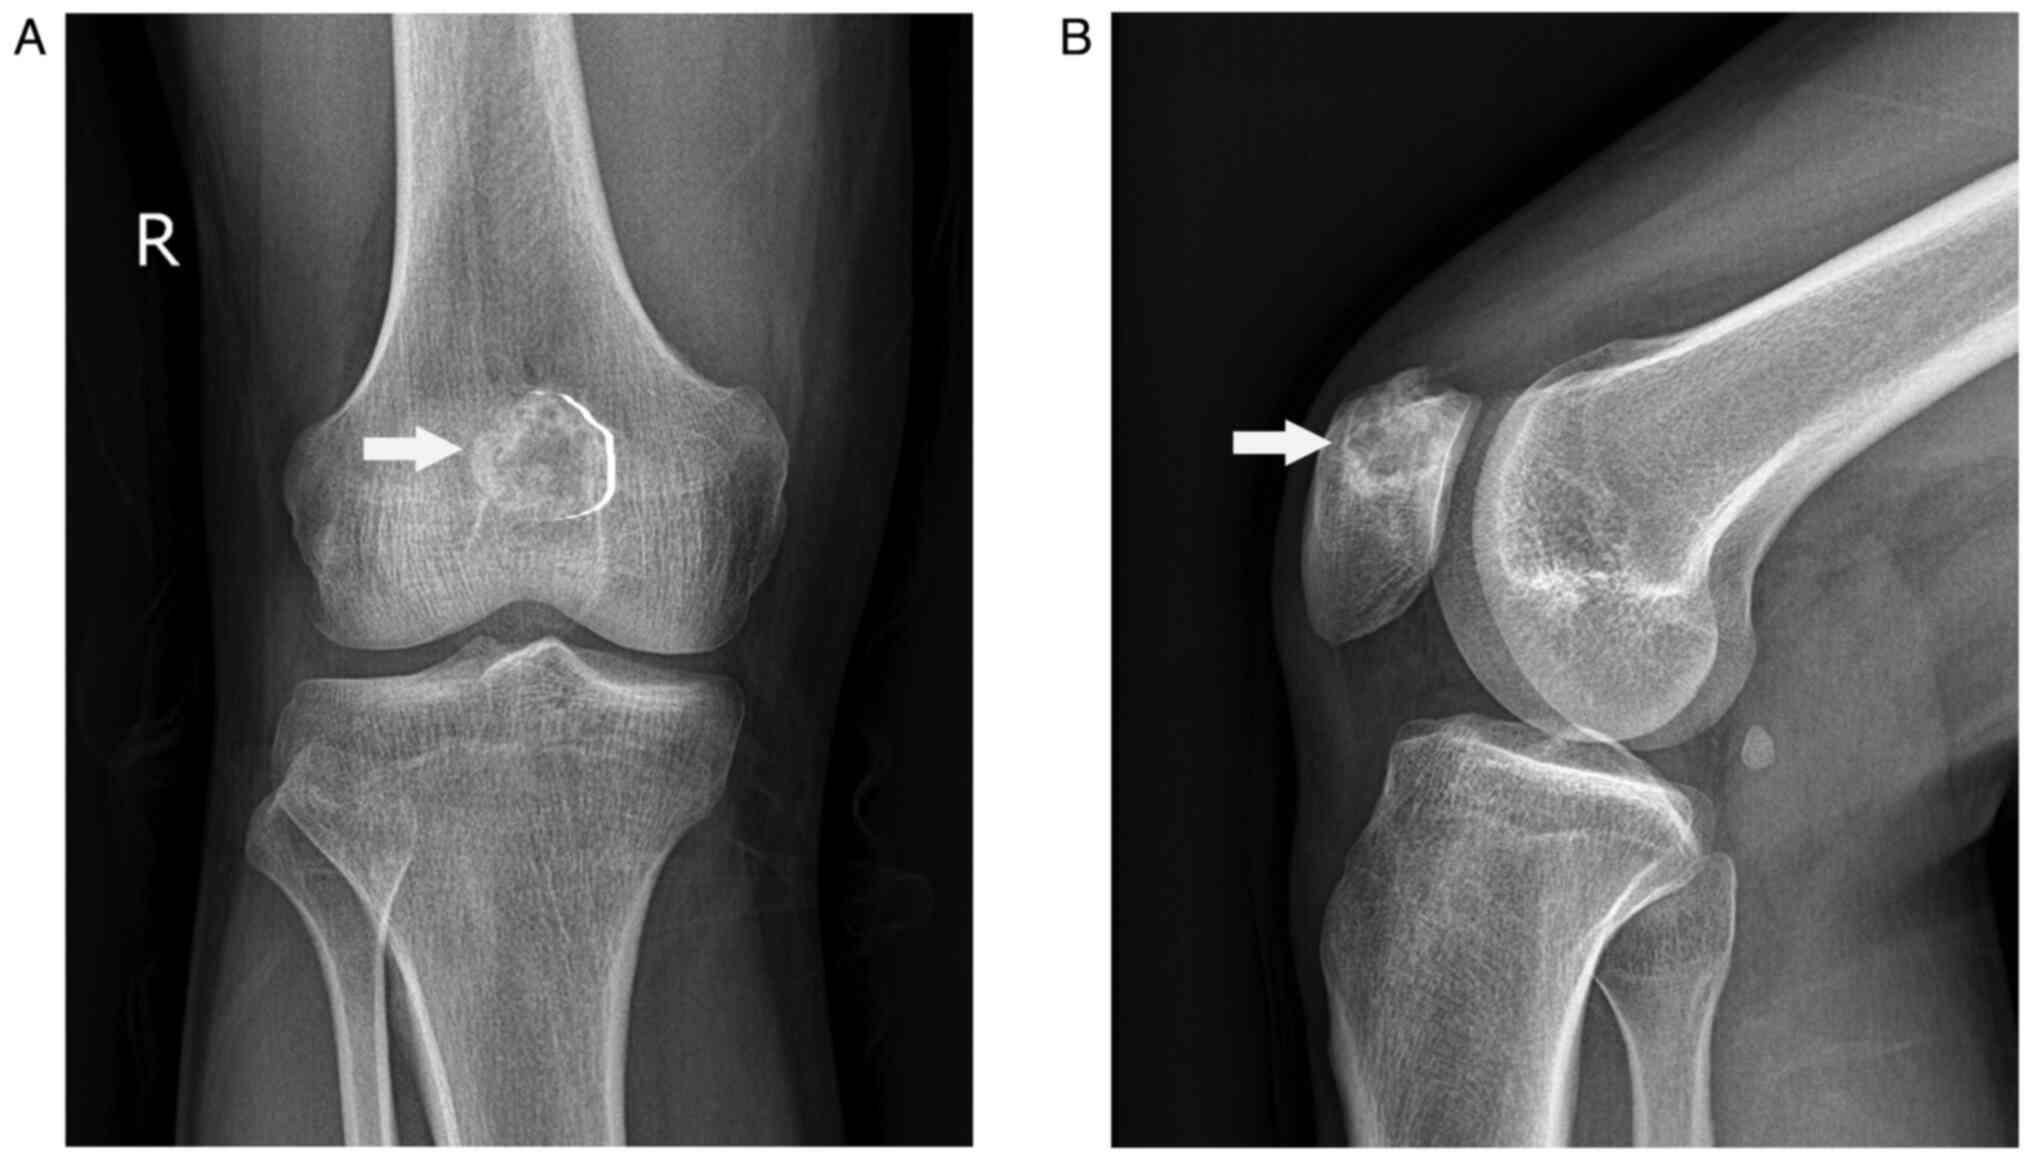

A 22-year-old male young adult was admitted to the 940th Hospital of Joint Logistics Support Force of Chinese People's Liberation Army (Lanzhou, Gansu, China) on December 5, 2020, with a 6-month history of intermittent pain in his right knee in absence of trauma. He did not have a significant personal or family medical history. His physical examination showed no obvious swelling or redness, and he had a normal skin temperature on the right knee. However, there was direct tenderness on the right patella. The range of motion of the right knee was full. The floating patella test, patella grind test, McMurray's test, anterior-posterior drawer test, and valgus-varus stress test were all negative. His neurological examination was normal. Laboratory tests revealed that his routine blood, liver function, kidney function, erythrocyte sedimentation rate, C-reactive protein, and tumor marker results were within the normal range. Radiography of the knee showed an osteolytic lesion at the medial superior quadrant of the right patella surrounded by a sclerotic margin with high density (Fig. 1). Computed tomography (CT) scan revealed a circular mixed-density image of the right patella that was surrounded by a thick sclerotic margin with high density (Fig. 2A). Three-dimensional CT showed no pathological fracture or cortical bone breakthrough (Fig. 2B and C). Magnetic resonance imaging (MRI) displayed a low-intensity signal mass on T1-weighted image (Fig. 3A) and high-intensity signal mass on T2-weighted image (Fig. 3B, C and D) with a well-defined lesion of the patella. Considering the clinical and imaging manifestations of the patient, benign bone lesions including chondroblastoma, osteoid osteoma, osteoblastoma, and bone abscess, were considered as the initial diagnosis.

Figure 2

CT scan showing a circular mixed-density image of the right patella surrounded by a thick high-density sclerotic margin with no evidence of extra-articular invasion. (A) Axial plane. (B) Frontal view of three-dimensional CT. (C) Lateral view of three-dimensional CT. CT, computed tomography.

The imaging manifestations of osteoblastoma differ depending on its location, and the results lack specificity. The most frequent X-ray manifestations of the osteoblastoma of the patella are that of an osteolytic lesion, with or without matrix mineralization and pathological fracture of the patella, surrounded by a high-density sclerotic margin with no evidence of extra-articular invasion (7,15). Aggressive spinal osteoblastoma can break through the bony cortex and invade the spinal canal and paravertebral soft tissue (16,17). CT scans are superior to MRI in showing calcification of osteoblastoma and thus are used to further confirm a well-defined lesion with fine calcifications. However, the radiological characteristics of CT are atypical. Tang P et al reported a case of osteoblastoma of the rib that was misdiagnosed as lymphomatous by CT and was confirmed by pathological examination (18). MRI helps in evaluating bone marrow edema and soft tissue component or extension of the tumor; however, there is no significant specificity to this finding.